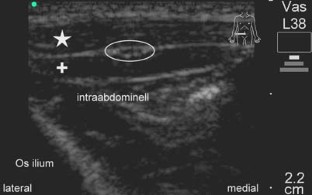

Abb. 3